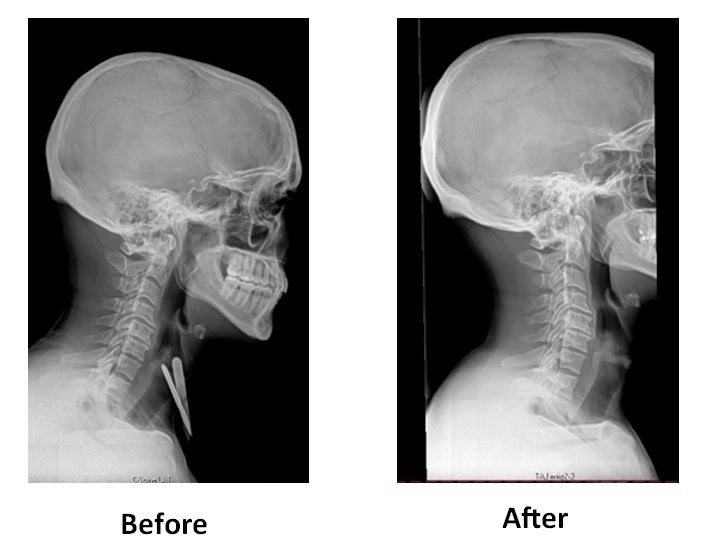

After a review of over 1,000 of my patient X-Rays I found a pattern. This pattern reflects the loss of the cervical curve in our necks from poor sleeping posture, yes, you read that correctly - back problems develop from POOR SLEEPING HABITS. This common loss is reinforced by our modern day lifestyle of texting and prolonged computer work, etc. Our bodies compensate by twisting our hips and throwing our lower backs out of alignment.

Maintaining proper curves of your spine is critically important in helping your body distribute stress when you walk or move. Another way to think about it is that the shape of your spine works like a big spring and acts like a shock absorber. When you lose the curves of your spine, you cause stress points within the spine, and as Davis Law states you will cause scar tissue to develop in those areas of the spine where you lose the curves. This restriction of motion in the joint leads to degeneration (arthritis) in that area.

As a culture, we are spending more and more time on computers, driving or texting on our phones. All of these positions are done in a forward head posture (head forward position). I find that the average person can spend up to eight hours a day in forward head position posture. This must be offset if you want to maintain a natural curve in your cervical spine.